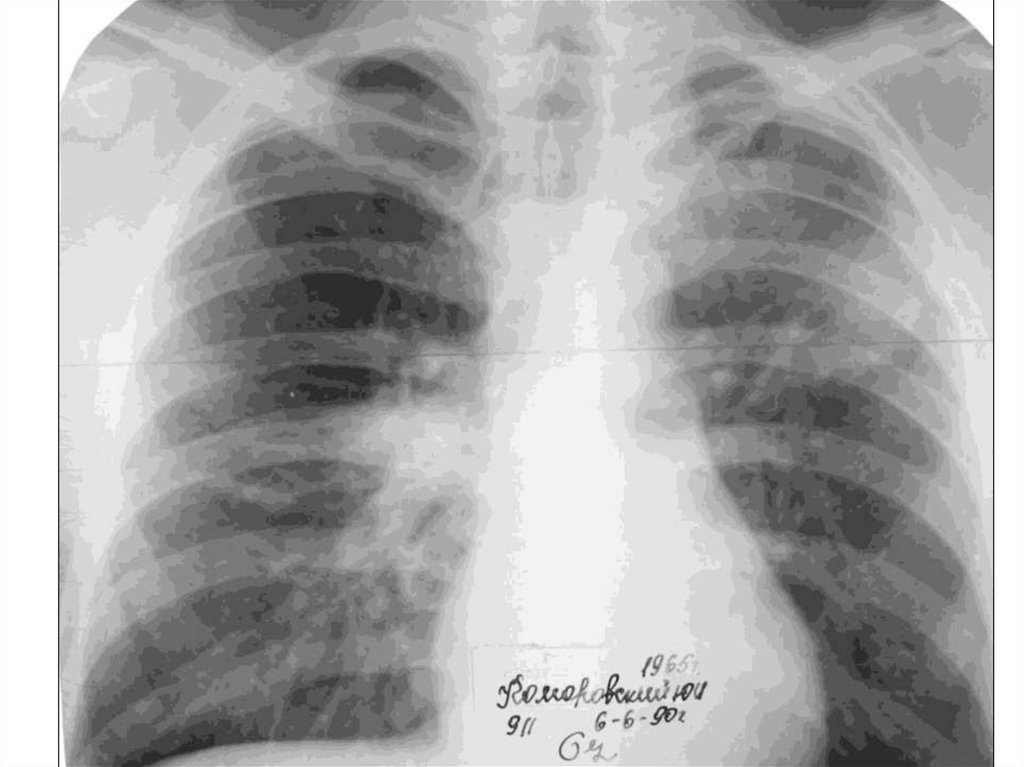

Иллюстрации по теме очагового и инфильтративного туберкулеза

Раздел: Фотодневник открытий